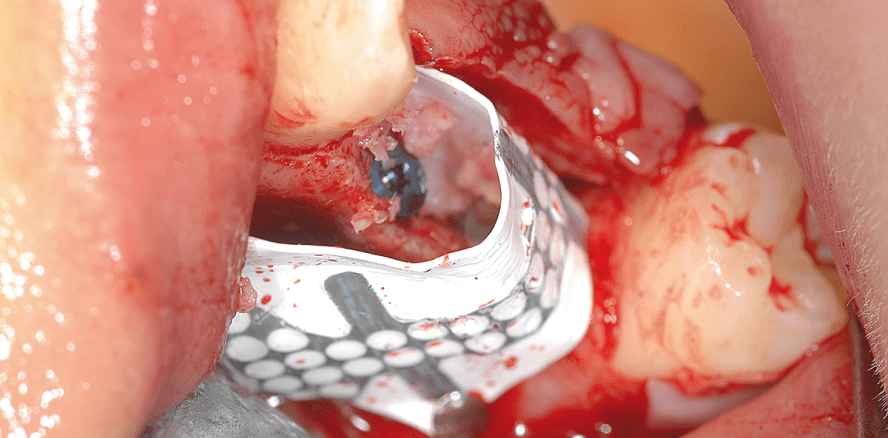

Es wurden ein Mukoperiostlappen abgehoben, Osteotomien auf der palatinalen Seite des Kieferkamms präpariert und zwei Implantate (Neoss ProActive® Straight, Neoss GmbH) gesetzt. Beide Implantatstellen zeigten Fenestrationen auf der bukkalen Seite (Abb. 2) sowie palatinale Dehiszenzen (Abb. 3). Im nächsten Schritt wurde eine titanverstärkte Membran zugeschnitten, geformt und an die Implantatstellen angepasst. Die Weichgewebeseite der Membran verfügt über eine dichte Textur, welche die Interaktion mit dem Weichgewebe fördert. Dies verleiht der Membran Stabilität und bildet eine Barrierefunktion, sodass das Risiko einer Infektion bei Membranfreilegung minimiert wird. Die Hartgewebeseite verfügt über eine expandierte Textur, die eine vorhersagbare Hartgewebe­integration ermöglicht. Zusammen mit der starren Netzkonfiguration kann eine vollständige Knochenauffüllung erreicht werden.

Mit autogenen Knochenchips, die beim Bohren der Implantatosteotomien gewonnen wurden, wurde die palatinale Dehiszenz aufgefüllt (Abb. 4). Es wurde kein Material zum Füllen der bukkalen Fenestration verwendet, die Festigkeit des Titannetzes schuf den Platz für die Knochenregeneration. Das Titannetz bildet eine Verstärkung, die während der gesamten Heilungsphase ihre Form behält. Die Membran wurde mit zwei Stiften bukkal fixiert (Abb. 5). Der Lappen wurde verschlossen und die Weichgewebeheilung verlief komplikationslos (Abb. 6).